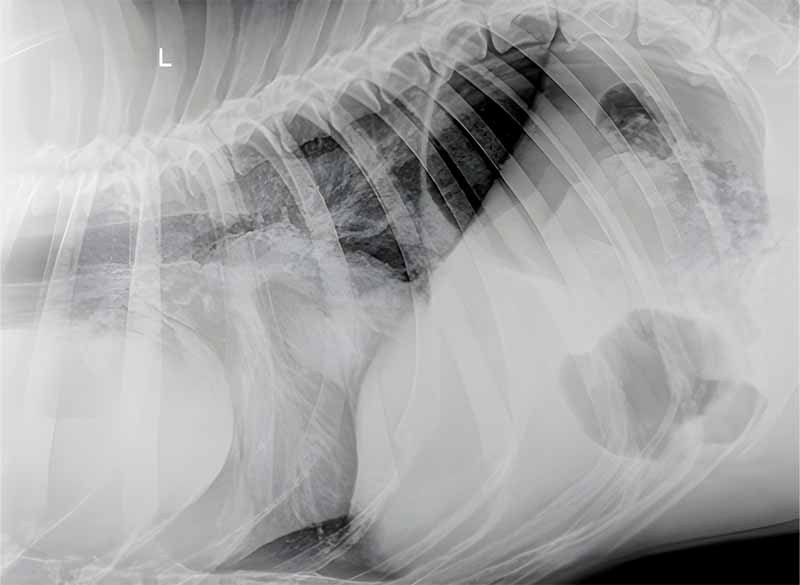

Paciente: Canino, raza Boxer, 11 años de edad.

Motivo de Consulta: Pérdida de peso severa y compromiso respiratorio.

Hallazgos Preliminares: La evaluación radiográfica torácica evidenció una estructura de densidad de partes blandas adyacente a la silueta cardíaca.